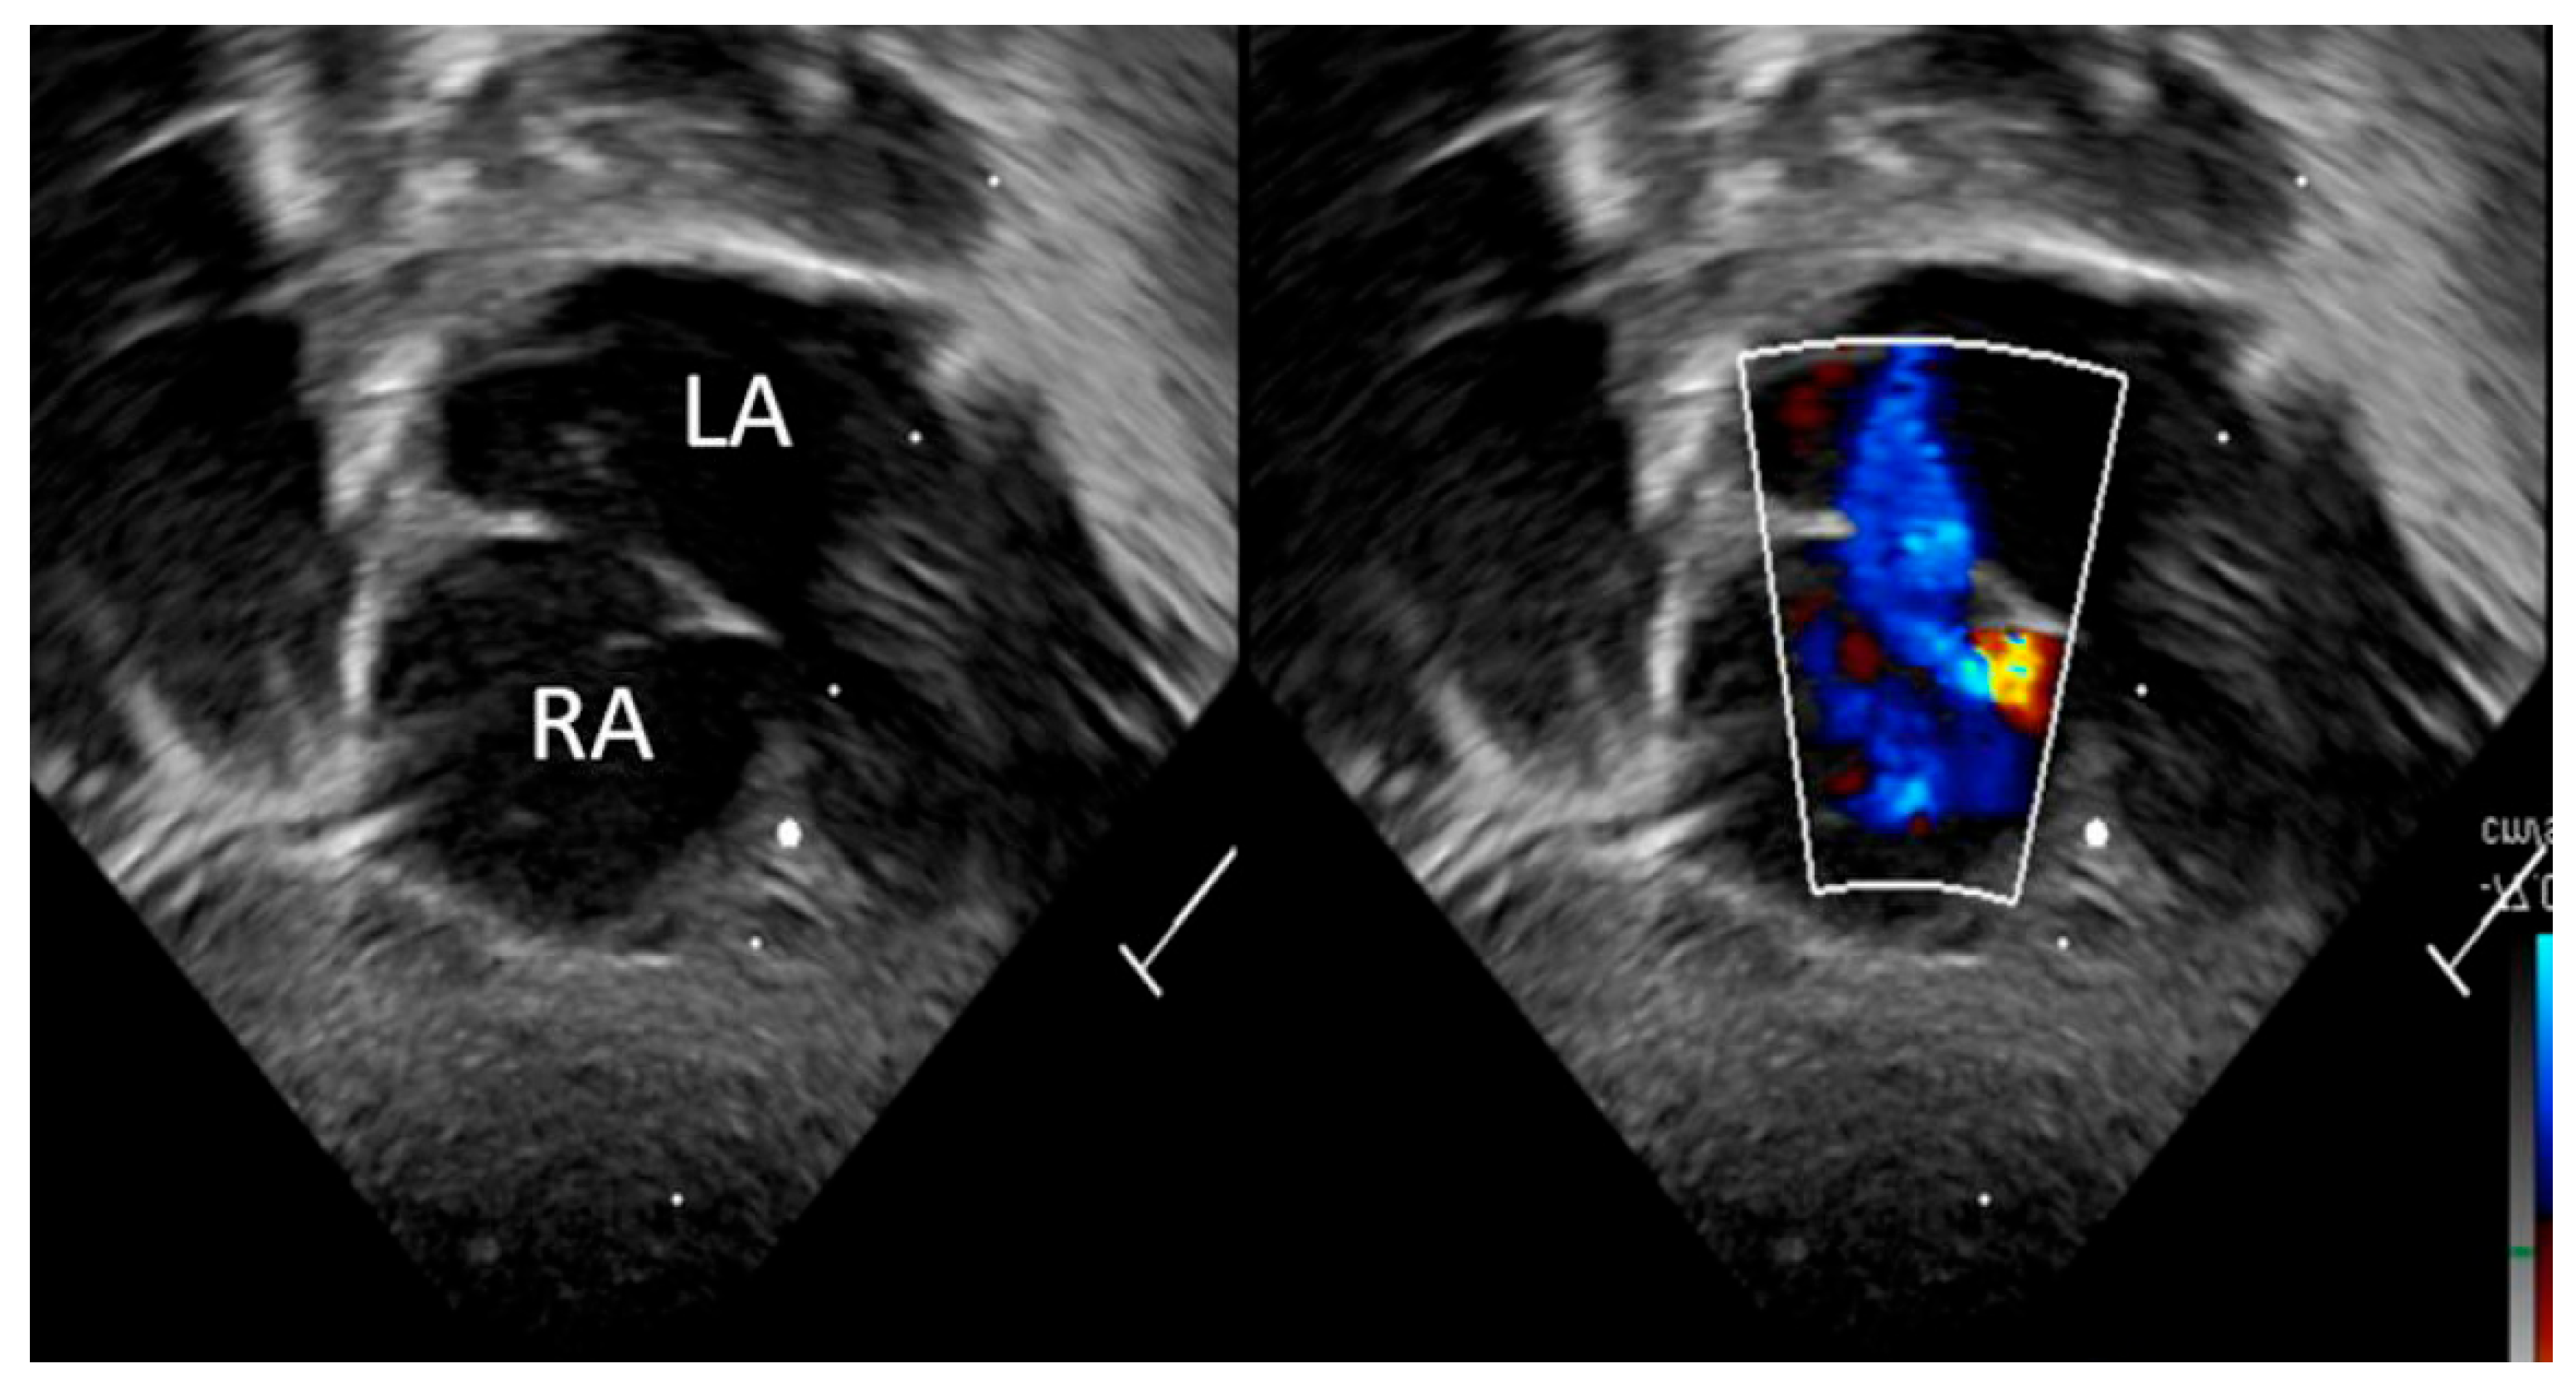

| Detection of Shunt | Identification and assessment of flow through the patent foramen ovale (PFO) and ductus arteriosus (PDA) | Indicates the presence and nature of pathological flow: left-to-right, bidirectional (often in moderate PPHN), or right-to-left (in very severe PPHN) |